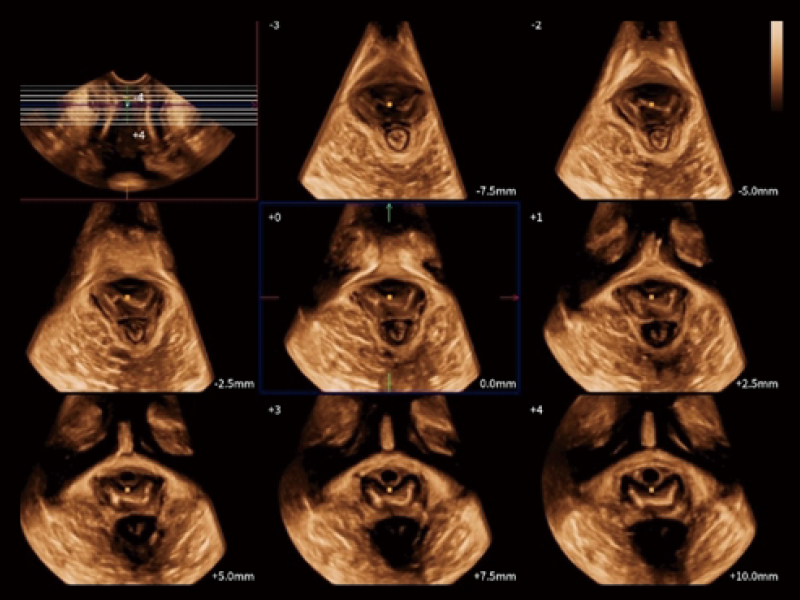

STIC

Auto M Slice for Levator Hiatus